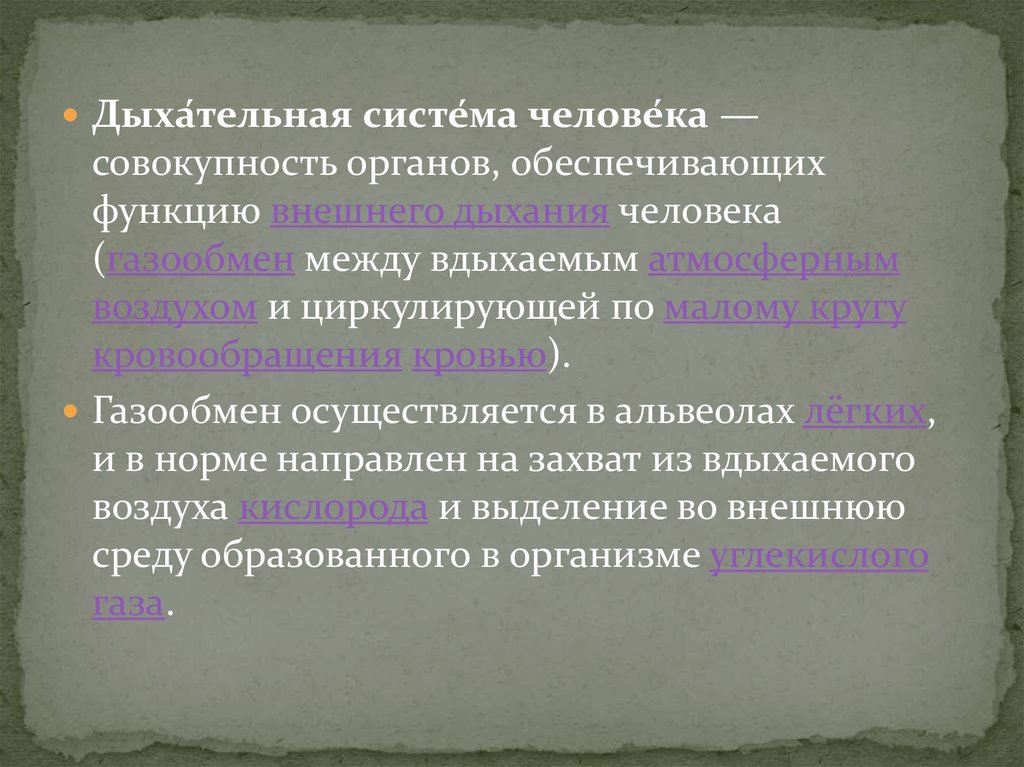

Дыхательная система (3) - Реферат , страница 1 . Дыхательная система человека - совокупность органов, обеспечивающих в организме человека внешнее дыхание, или …

Дыхательная система выполняет жизненно важную функцию — обеспечение клеток организма кислородом и освобождение их от углекислого газа, являющегося конечным продуктом …

Основной механизм регулирования дыхания — центральная нервная система . Дыхательный центр регулирует частоту и ритм дыхания .